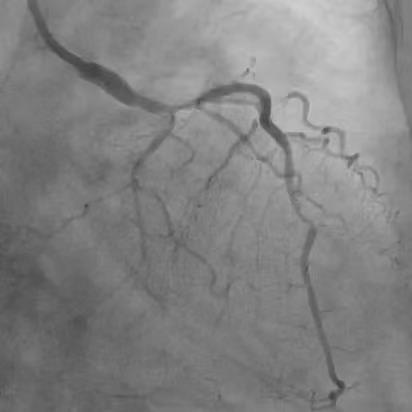

患者74岁,10年前因胸痛诊断为冠心病,在外院放过支架,但当时医生即明确告知家属,血管最严重的“总开关”左主干的地方钙化分叉,处理起来太危险,只是把难度相对不高的血管放了支架。近年来患者间断胸闷、胸痛,伴有心衰下肢肿胀,辗转来我院。冠脉CT显示冠脉严重钙化,因此安排冠脉造影检查。 ![]() ![]() 术前CTA提示左右冠支架术后且左主干重度钙化 (主干没有支架) 冠脉造影

![]() ![]() ![]() 左右冠脉造影:右冠脉支架远段已完全闭塞,旋支远端完全闭塞,前降支中远段重度狭窄,左主干重度钙化分叉。 手术策略